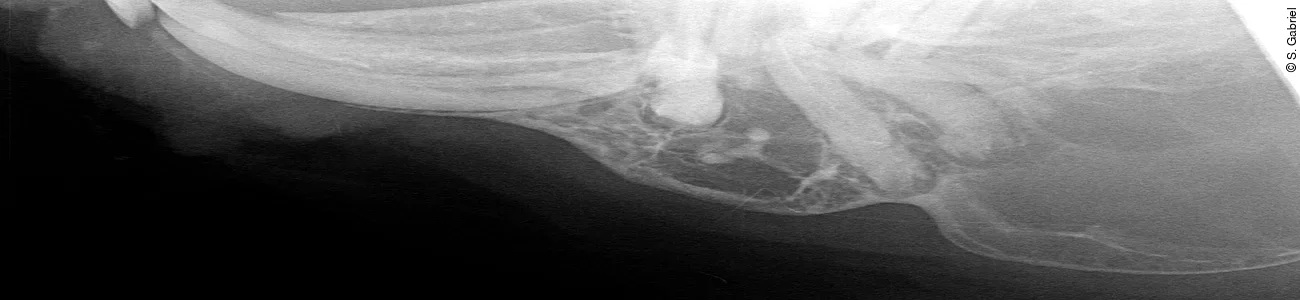

Eine Besonderheit der Unterkieferabszesse bei Kaninchen ist, dass auch in chronischen Fällen mit weitreichender Lyse der Spongiosa und Blasenbildung offenbar noch Zahnwachstum stattfinden kann. Weil es der Körper offenbar nicht schafft, die Abszessursache durch Eiterabfluss nach außen zu entfernen, beobachtet man nicht selten gespaltene oder deformierte Zahnkörper oder Dentinoide in skurrilen Formen inmitten der Eitermassen. Logischerweise wirken diese als Fremdkörper und schüren die Abszessbildung weiter. Das unterstreicht noch mal die Bedeutung guter Röntgenaufnahmen für den Operationserfolg!

Handelt es sich um einen teilweise mit dem Periost verwachsenen oder bis in die Unterkieferspongiosa reichenden Abszess, ist die vorsichtige Resektion der Kapsel bis aufs Periost zu empfehlen. Mit einem scharfen Löffel kürettiert man danach die im Knochen liegenden Anteile der Abszesskapsel ([Abb. 3 a]). Falls die Kapsel an ihrer Basis durch periostale Auftreibungen schon knöchern durchgebaut ist, können die ossifizierten Anteile des Periosts mithilfe einer Luerschen Zange („Mini-Friedmann“) reseziert werden ([Abb. 3 b]). Dabei ist grundsätzlich darauf zu achten, die Stabilität des Unterkiefers nicht weiter zu reduzieren und nur vorragende Knochenspitzen für eine bessere Wundheilung abzusetzen. Auch für diese Entscheidung ist eine gute Röntgendarstellung unabdingbar ([Abb. 1]).